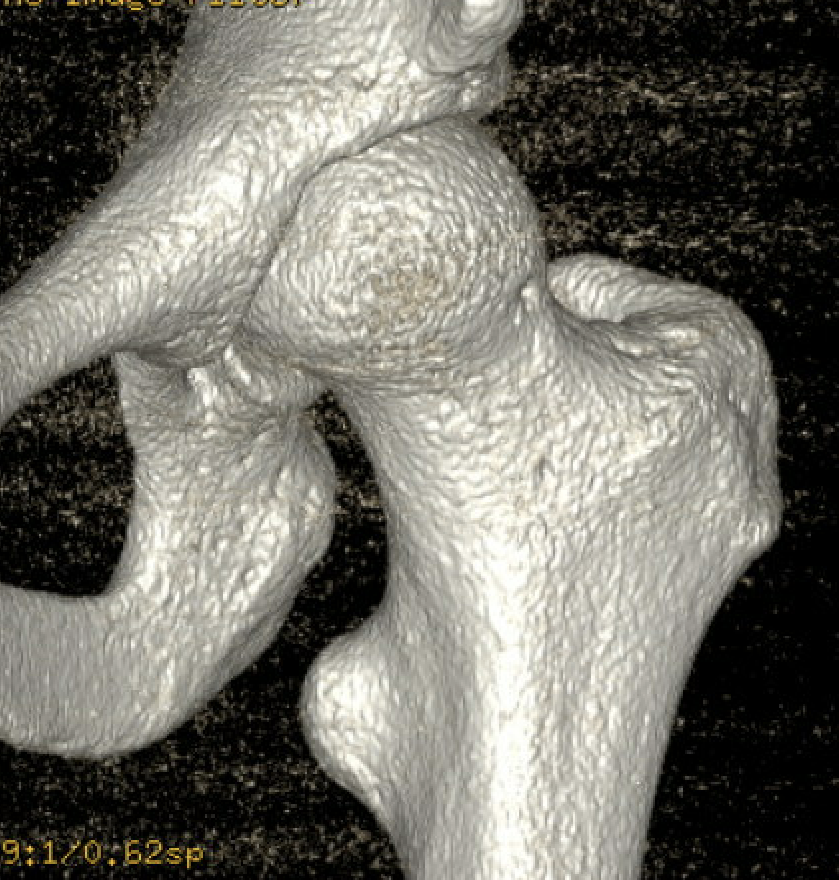

CT

IFI

IFIIFIIFI